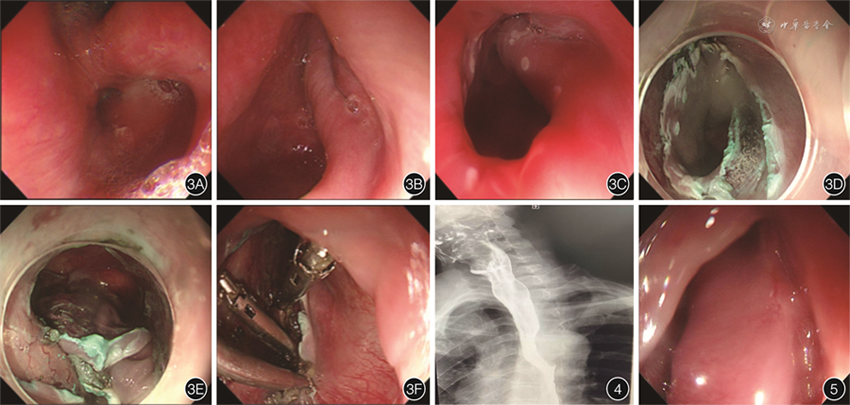

患者男,62岁,因“上腹部疼痛,进食后呛咳1月余”收治入院。患者吞咽困难、声音嘶哑、口气,伴咳嗽、气短,自诉平时进食伴吞咽不畅、吞咽疼痛,入睡后颈部有气泡声,说话时有突然失音。吞咽困难评分为3分(0分,可正常饮食;1分,能进食部分固体食物;2分,只能进食半流质;3 分,只能进食流质;4分,无法进食)。入院前行钡剂造影检查显示食管上端偏右侧壁见囊袋状存钡影,直径约4.9 cm,余食管各段及贲门未见明显异常,诊断为Zenker憩室(图1),颈部磁共振平扫+增强检查示食管上段憩室(图2)。拟行内镜下憩室内黏膜剥离术联合金属夹封闭术治疗。患者在术前1周停用抗凝药物和抗血小板聚集药物,具体手术过程(图3、视频)如下:(1)在完成气管插管和麻醉后,用Dual刀在距门齿16 cm处的憩室口进行内镜标记。(2)黏膜下注射生理盐水、亚甲蓝和肾上腺素混合物抬高憩室内黏膜。(3)黏膜切开刀沿标记点将憩室内部黏膜预切开并行黏膜下剥离,该患者剥离至憩室底部时,黏膜下层粘连明显,局部黏膜下层提升不良,在此处紧贴固有肌层进行剥离,剥离完成后无明确穿孔。(4)黏膜下剥离完成后,用金属夹封闭憩室开口,修复食管壁肌层。(5)内镜下放置胃管,结束手术。术后立即给予抗感染(头孢哌酮钠舒巴坦钠)、鼻饲营养支持、抑酸补液等处理。术后患者无明显疼痛和发热,自诉颈部异响、口气、声音嘶哑、进食困难、咳嗽、气短等症状消失,于术后第三天带胃管出院。半月后患者复查钡剂造影示憩室腔完全闭合(图4),拔除胃管,逐步过渡至正常饮食。术后3月余复查胃镜(图5)示憩室腔消失,吞咽困难评分为0分。随访至2023年4月30日,患者无不适。